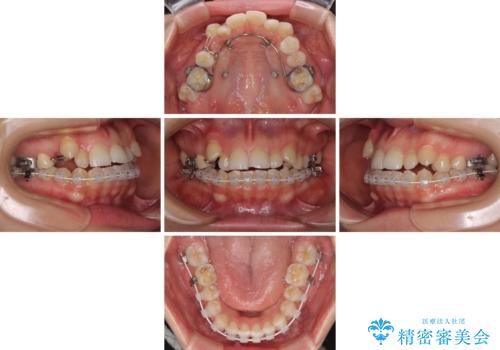

目立ちにくい抜歯矯正 ハーフリンガル

- ハーフリンガル

- 前歯のデコボコや八重歯、舌癖による開咬を気にして来院された患者様です。

目立たない装置を希望されたので、上顎が裏側装置のハーフリンガルを選択し、上顎小臼歯1本を抜歯して、補助装置を併用して矯正治療を行うこととしました。

補助装置を事前に使用したことで、あっという間に八重歯が改善し、ハーフリンガルにしては1年半もかからずに治療を終えることができました。